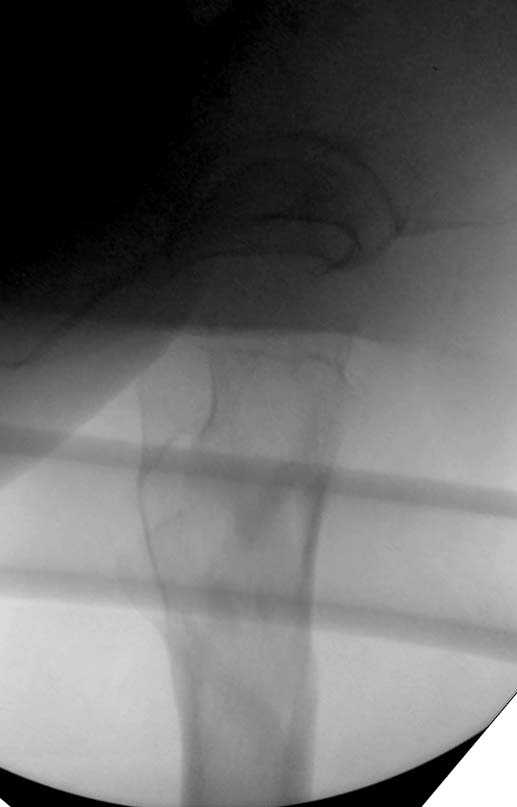

При первом послеоперационном поликлиническом осмотре больная предъявила жалобы на боли в бедре. В серийных снимках обнаружен продольный перелом верхнего отдела бедра.

Считаем, что техническая ошибка произошла во время установки гвоздя, когда рассверливанию канала не уделили должного внимания. Канал остался узковат, и гвоздь был забит с силой. Полная нагрузка конечности приостановлена на две недели, и боли в конечности изчезли. Больная начала нагрузку и перелом срастается.-- Djoldas Kuldjanov, M.D.Associate ProfessorDepartment of Orthopedic SurgerySt. Louis University

I looked at the films again and saw that you are referring to the nondisplaced shaft fracture, not the proximal fragment position. Sorry.

Мне думается, что варусное положение проксимального отломка на последующих снимках не более чем проекционный феномен. Раскол же диафиза вдоль, наверняка, связан с чрезмерно насильственным введением штифта. Вообще, при реверсивных, да и обычных вертельных переломах, многие давно отказались от короткой Гаммы в пользу long-версии. Но в любом случае надо быть на 100 уверенным в подготовке канала.